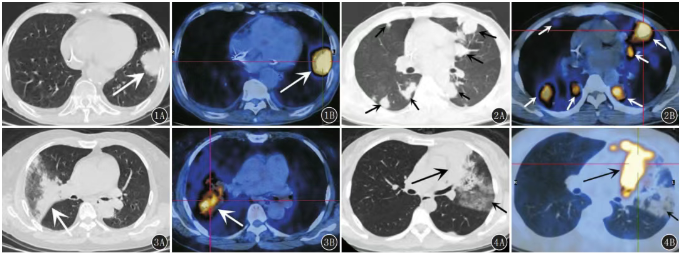

在消化道肿瘤的诊断、分期与疗效评估中,PET/CT凭借其独特的代谢显像能力,已成为关键影像手段之一。其原理在于利用肿瘤细胞通常代谢活跃、摄取更多葡萄糖类似物(如¹⁸F-FDG)的特性,在图像上呈现“代谢增高”,从而与CT提供的精细解剖结构相结合,实现“形态”与“功能”的双重评估。这种“全身一站式”成像方式尤其适合评估易发生转移的消化道肿瘤,可同步检测原发灶、淋巴结转移及远处器官(如肝、肺、骨)的转移情况,在肿瘤性质判断、分期及复发监测中提供重要依据。

在不同类型消化道肿瘤中,PET/CT具有明确的应用指向。在食管癌中,它主要用于术前分期、新辅助治疗后疗效评价及复发监测;在胃癌中,其对远处转移灶的检出和化疗效果评估具有较高价值;在结直肠癌中,PET/CT能有效检出肝转移等远处转移,协助判断手术可切除性,并鉴别术后改变与肿瘤复发;而对于胰腺癌及胆道肿瘤,PET/CT可辅助检测常规影像不敏感的转移灶,其代谢信息常在结构改变前提示异常。临床实践证明,PET/CT所提供的代谢信息,常比单纯形态学变化更早反映治疗反应,从而帮助临床及时调整治疗方案。